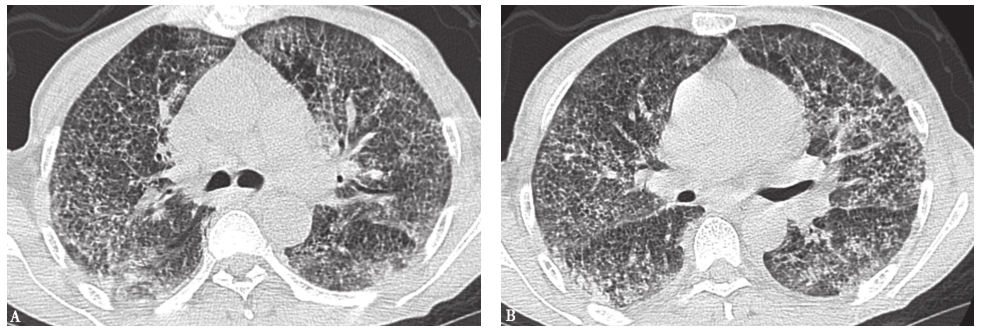

17个月前胸部CT见双肺弥漫性小结节(图1)。

图1 17个月前胸部CT表现